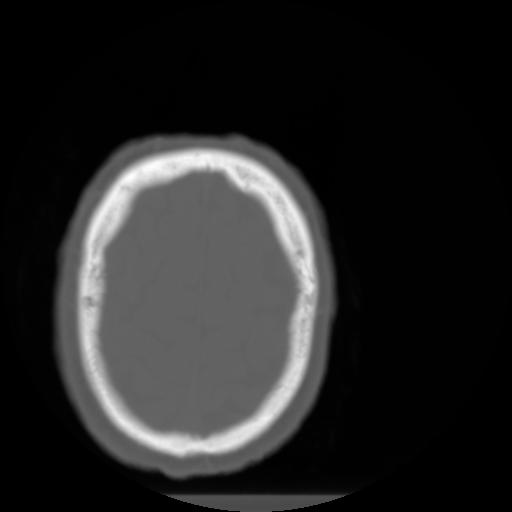

3 CEREBRO,,Axial,3.0,CEREBRO,,